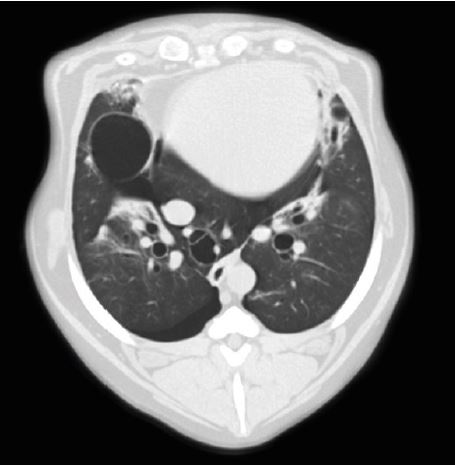

Діафрагмальна грижа

Чіткі, різкі зображення з високою роздільною здатністю необхідні для встановлення найточнішого діагнозу. А швидке отримання та інтерпретація оптимізує робочий процес і має важливе значення в екстрених ситуаціях. Ви можете досягти високої якості зображення швидше за допомогою багаторядного детектора PUREVision від Aquilion, який має на 40% більшу світловіддачу порівняно з іншими системами. Це єдиний доступний багаторядний детектор з фактичною роздільною здатністю 0,5 мм. Справжня ізотропна роздільна здатність унікального детектора Aquilion PUREVision дозволяє проводити багатоплощинні реконструкції з найвищою просторовою роздільною здатністю у всіх площинах.